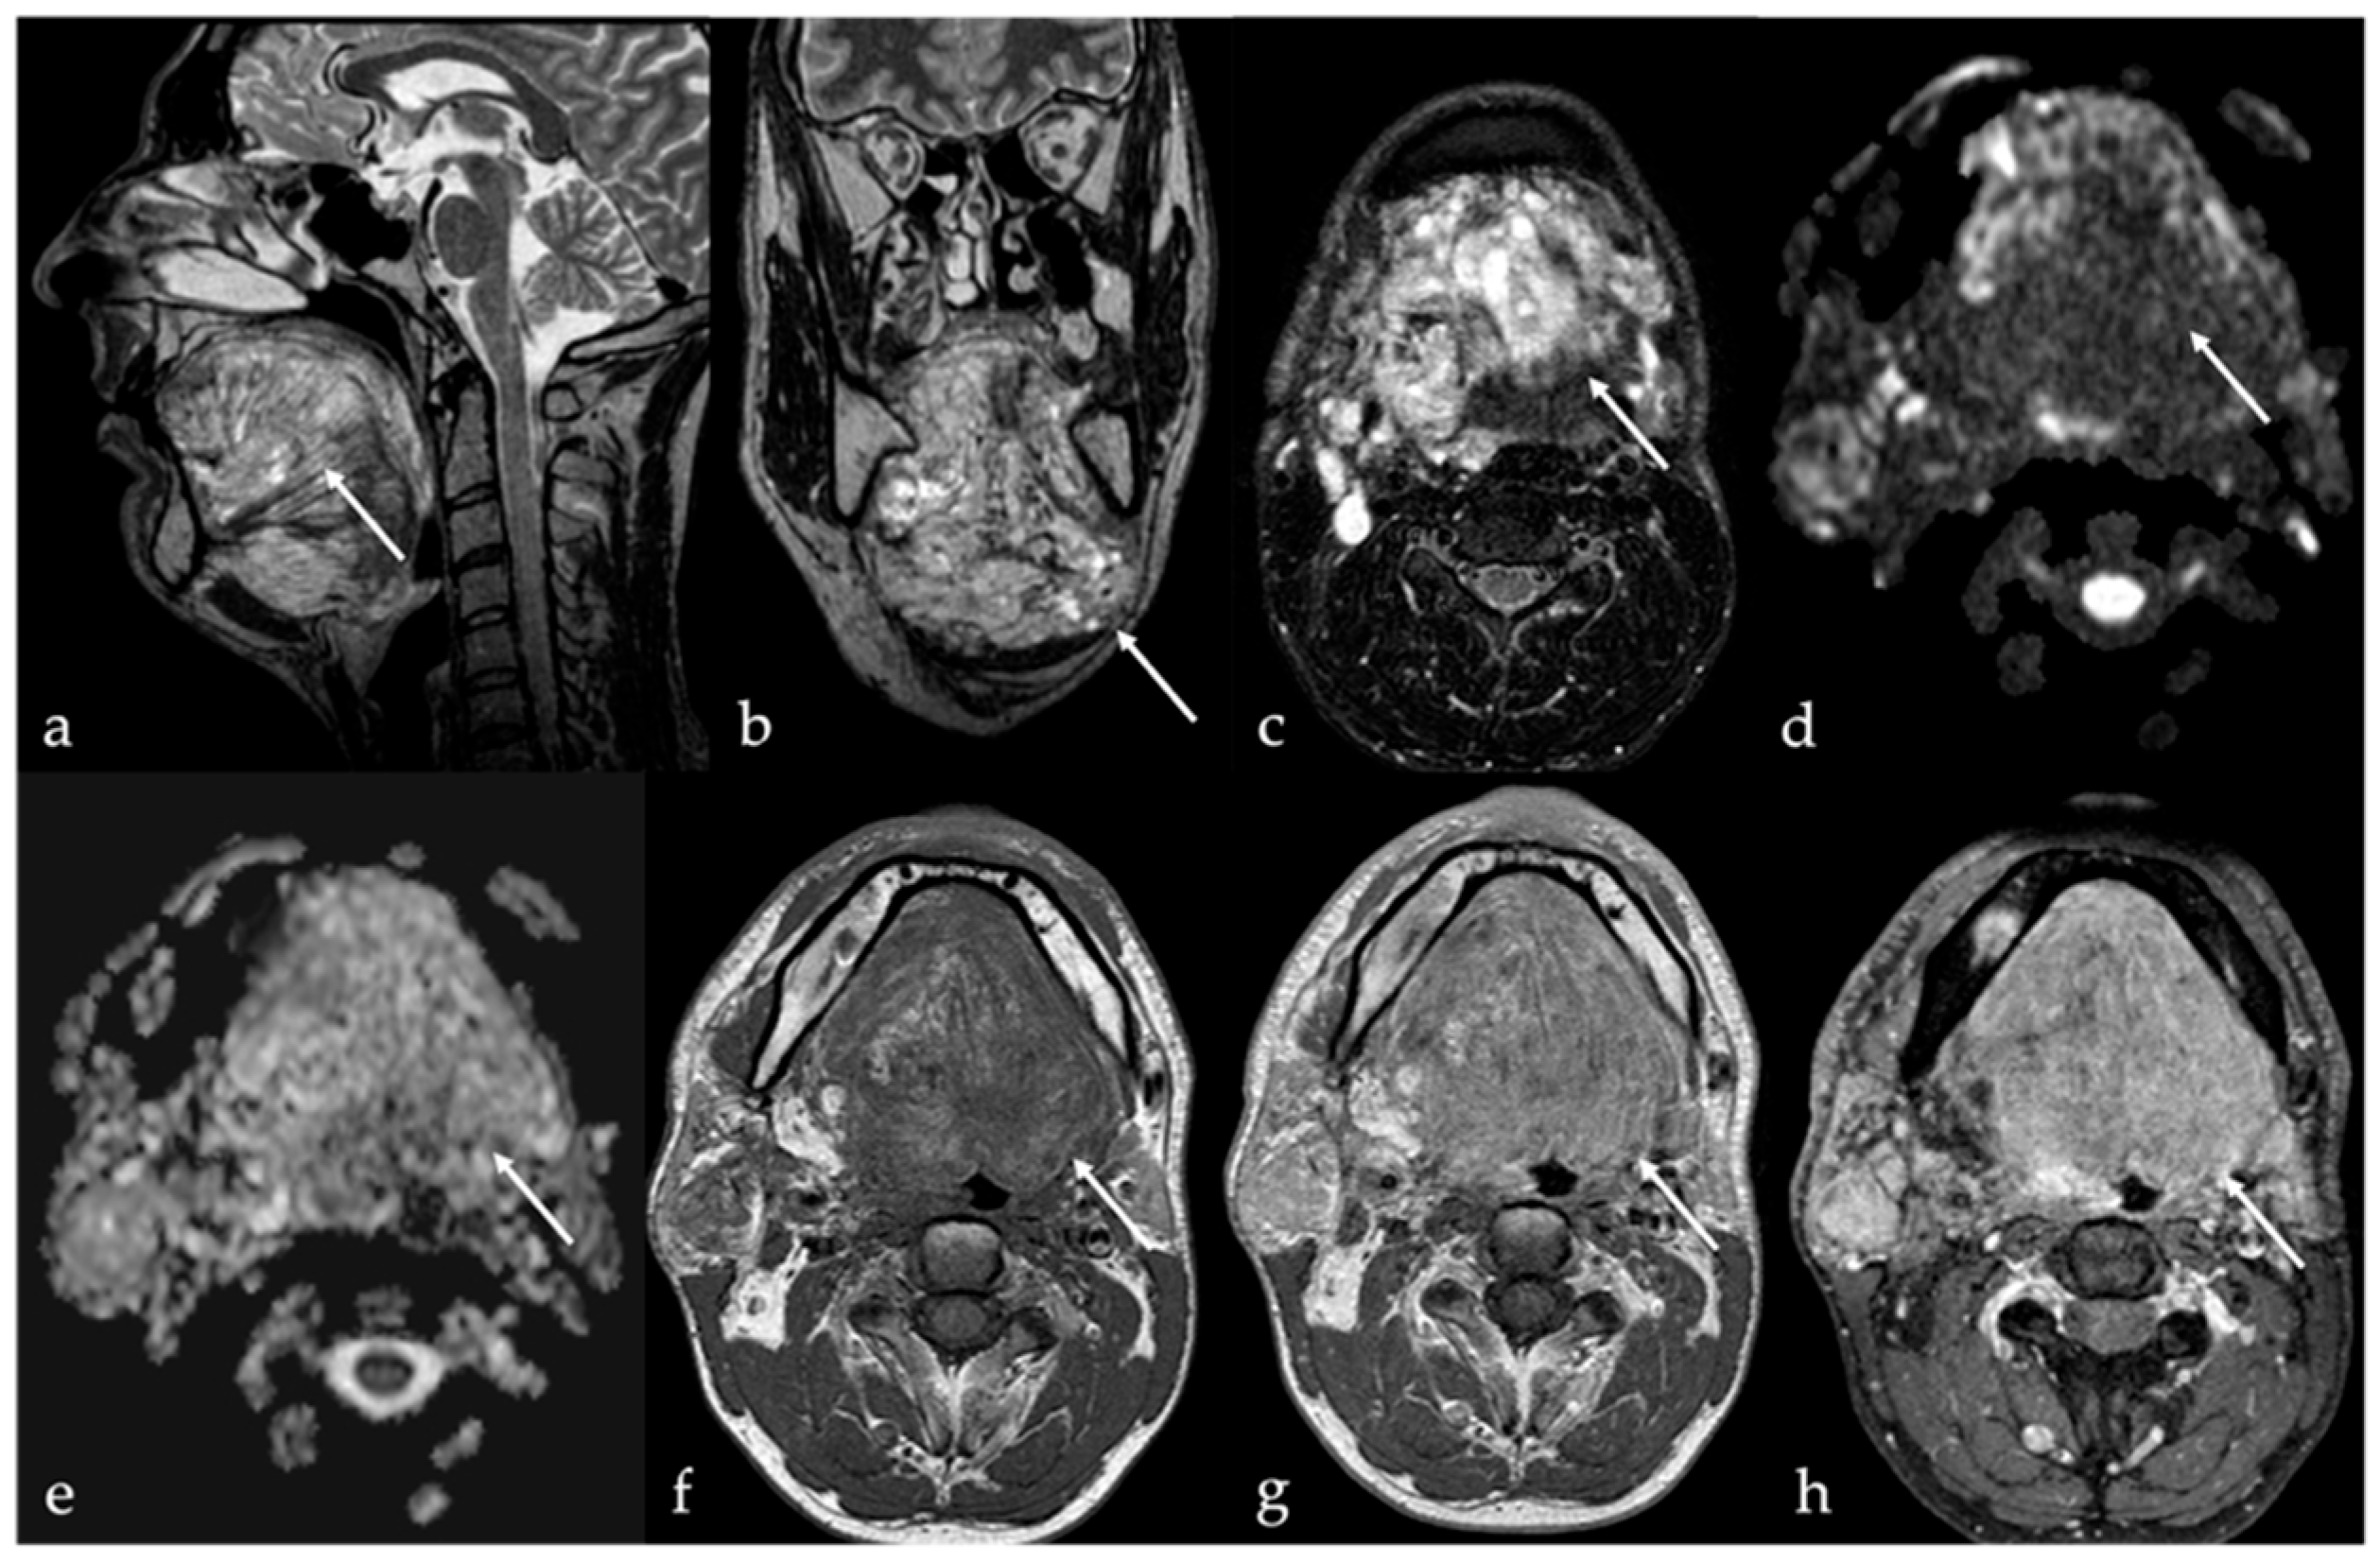

5.2. Lymphatic Malformations

5.3. Arteriovenous Malformations

| Lymphatic malformation [10,11] | Unilocular or multilocular, microcystic (<1 cm) or macrocystic (>1 cm) CT, MRI: no solid nodule with +CE MRI: high T2 SI, fluid-fluid levels | Other vascular malformations, dermoid cysts |

| Arteriovenous malformation [6,12] | MRA: arterial feeding vessel, nidus, and venous drainage vessels MRI: flow voids | Other vascular malformations |